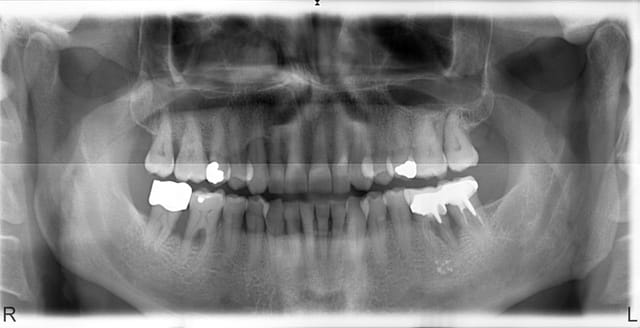

Patient 54 ans

non fumeur

douleur zone 46 47

suppuration 36

hbd acceptable

Pour moi 46-47 c'est pas conservable et au risque de perdre encore un peu plus d'os. 36 je ne vois pas la racine mésiale sur ta pano. La distale est condamnée. Si possible de garder la racine mésiale et faire un bridge avec la 37. Celà dépendra de la possibilité de refaire le traitement canalaire( encore que les racines mésiales sont plus difficiles à conserver par rapport aux distales. Sinon et avant tout assainissement global avant d'extraire.

Et le maxillaire tu fais rien?

Image de perte osseuse sur 13 et 27 qui sont importantes.

la 27 me semble compromise qu'auriez vous fait